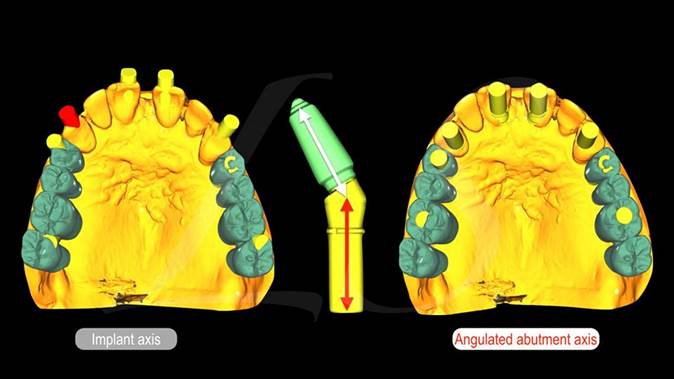

Clinical case: Extraction, immediate implant placement, & provisionalization

- Courtesy of Dr. Iulian Filipov, Romania -

AnyRidge, R2GATE, guided surgery, immediate placement, immediate provisionalization, initial stability, Dr. Iulian Filipov, #25, maxillary posterior, immediate loading, Mega ISQ

AnyRidge implant system, R2GATE, MEGA ISQ, Digital prosthesis